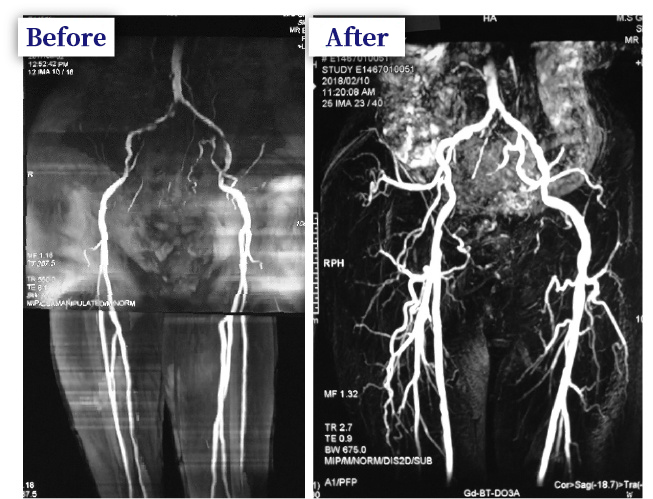

治療実例 74歳 男性 Eさん

歩行痛を訴え来院。MRAに示してあるように明らかに血管の狭窄がみられた。

金点滴療法を施術すると血流が明らかに改善した。

痛みの症状もほとんどとれたという。